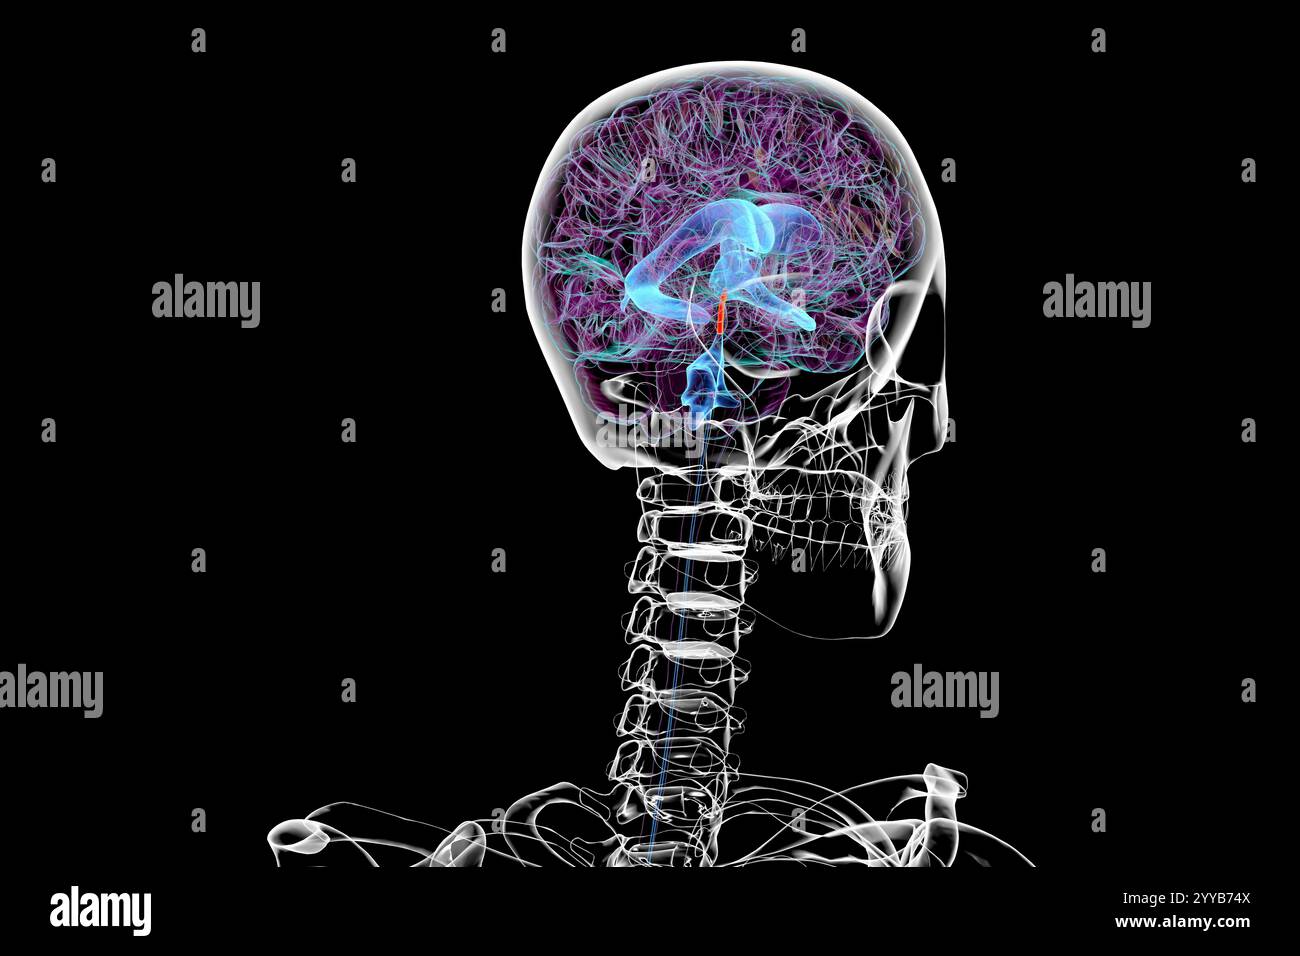

RF2T7NGWH–Ventrikel und zerebrales Aquädukt laterale Röntgenansicht 3D-Rendering-Illustration. Menschliches Gehirn und Ventrikelsystem Anatomie, Medizin, Gesundheitswesen, Scienc

RF2T7NGWK–Ventrikel und zerebraler Aquädukt lateral in Farben Röntgenbild-3D-Rendering-Illustration. Menschliches Gehirn und Ventrikelsystem Anatomie, medizinisch, gesund

RF2T7NGWR–Ventrikel und Hirn-Aquädukt-Röntgenprofil Nahansicht 3D-Rendering-Illustration mit Körperkonturen. Anatomie des menschlichen Gehirns und des Ventrikelsystems,

RF2T7NGWW–Ventrikel und zerebraler Aquädukt in Farben Röntgenprofil Nahansicht 3D-Rendering-Illustration. Anatomie des menschlichen Gehirns und des Ventrikelsystems, medizinisch,

RF2T030FH–Röntgenprofilansicht des Sylvius oder des zentralen Aquädukts des Gehirns 3D-Rendering-Illustration. Menschliche Körperanatomie, Medizin, Biologie, Wissenschaft, Neurowissenschaft,

RF2T6AR8J–3D-Rendering-Illustration für die Röntgenansicht des Gehirns oder des Sylvius aquädukt. Anatomie des menschlichen Gehirns und des Ventrikelsystems, Medizin, Gesundheitswesen, Biologie, Wissenschaft,

RF2T6AR96–Röntgenprofil des Gehirns oder sylvius aquädukt Nahansicht 3D-Rendering-Illustration mit Körperkonturen. Anatomie des menschlichen Gehirns und des Ventrikelsystems, med

RF3C7H8A6–Abbildung des Gehirns mit hervorgehobenem Aquädukt (rot) und ventrikulärem System (blau), Darstellung des Liquorflusses.

RF2YYB751–Computerdarstellung des cerebralen Aquädukts (orange), eines schmalen Kanals im Mittelhirn, der den dritten und vierten Ventrikel verbindet und den Liquorfluss erleichtert.

RF2YYB74X–Computerdarstellung des cerebralen Aquädukts (orange), eines schmalen Kanals im Mittelhirn, der den dritten und vierten Ventrikel verbindet und den Liquorfluss erleichtert.

RF2YYB75A–Computerdarstellung des cerebralen Aquädukts (orange), eines schmalen Kanals im Mittelhirn, der den dritten und vierten Ventrikel verbindet und den Liquorfluss erleichtert.